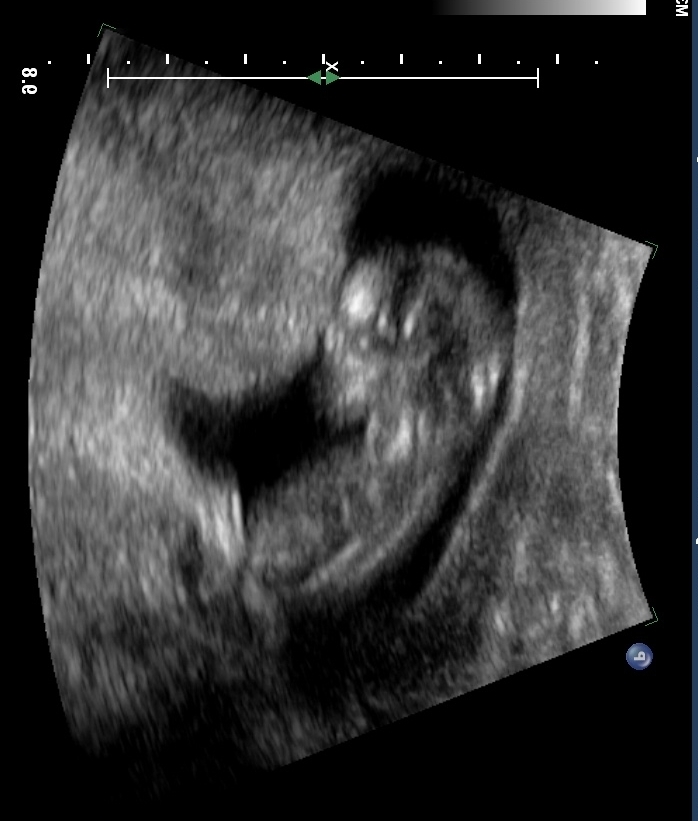

Was told on another site there was no nub but wanted more opinions. Thanks Attachment 13489

No doubt from this pic? There's no nub!

Nope, no nub seen. Sorry!